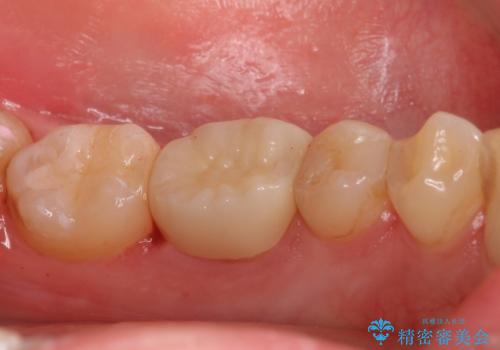

歯の高さがなく、またセラミックアンレーは割れるリスクが高いため、セラミックのアンレーとはせず、クラウンとし、さらに割れにくいようにヴェレッツァクラウンとしました。

- 合計 17.6万円(内訳 左下7:e-max インレー 7.7万円、左下6:セラミッククラウン(ヴェレッツア 8.8万円)、仮歯 1.1万円)費用は治療当時の料金となります

裏側の歯ブラシも当たっておらずプラークが多く付着していたため合わせて歯磨き練習も行いました。